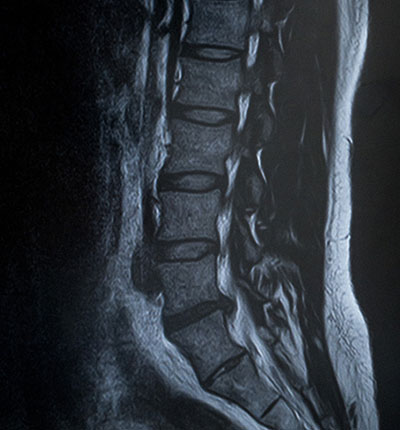

腰骨や背骨の変形や骨折が原因となる脊柱管狭窄症、変形性腰椎症、椎間板ヘルニアや脊椎分離すべり症、圧迫骨折などから来る腰痛があります。

これら変形により逸脱した骨が周辺の神経や筋肉を含む軟部組織を圧迫し痛みが出ます。

「脊柱管狭窄症」

反り腰姿勢などから背骨・骨盤のゆがみや腰の靱帯の緩みが起き、脊髄神経が圧迫され、腰が痛んだり、足にしびれが出て歩きにくくなったりする症状がでます。

「変形性腰椎症」

加齢により腰骨が変形していき、骨の角にトゲ(骨棘)ができたり、骨と骨との間にある軟骨がすり減って痛みを出します。

「椎間板ヘルニア」

猫背姿勢などで腰骨の丸まりが強くなった時に骨と骨の間にある椎間板が圧迫され、逸脱した椎間板が神経を圧迫して痛みやシビレが出ます。

「脊椎分離すべり症」

主にスポーツを行う若年層に発症しやすいもので、反り腰があったうえで激しい動きを繰り返していると、背骨の椎間関節というところに骨折が起き、スポーツが続けられないような強い痛みが出ます。走り幅跳びや体操競技選手などに起きやすい症状です。

images

その中でも椎間板ヘルニアの場合、腰が丸まっていると椎間板の圧力が増し、痛みが強くなる要因となります。

脊柱管狭窄症狭窄症や脊椎分離すべり症は逆に腰が反りすぎていると痛みが強く出ます。

このように腰痛の病態により対処法も変わってくるので、姿勢やその方の背骨がどのように歪んでいるかを診ていくことが大切です。